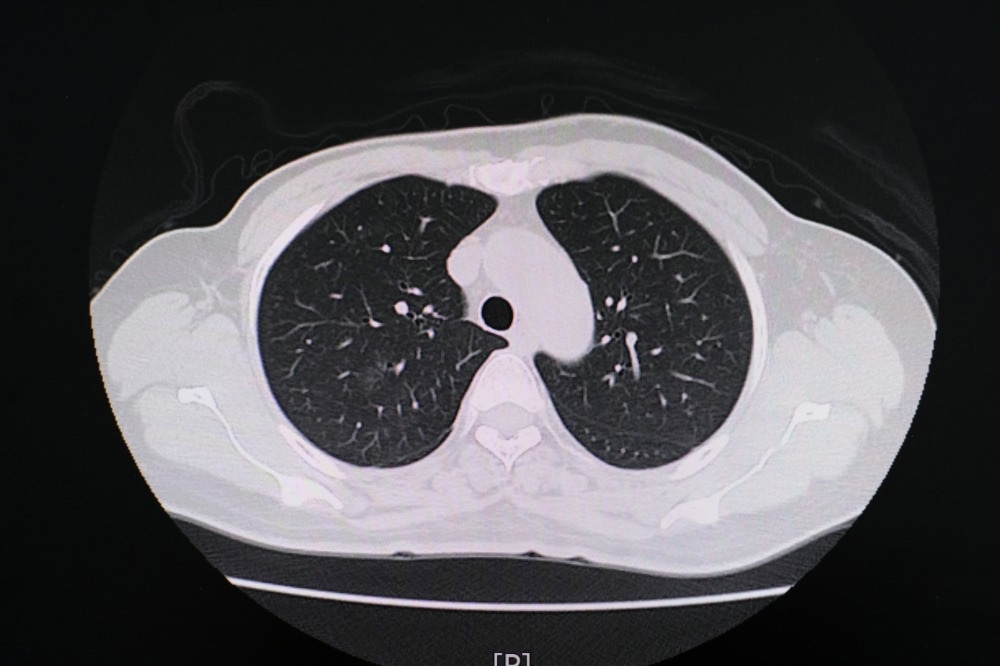

Study: Chest CT Findings in Marijuana Smokers. Image Credit: PIJITRA PHOMKHAM / Shutterstock.com

In addition to pulmonary function tests, CT lung imaging can also provide important information on the impact of marijuana smoking on the lungs.

As compared to non-smokers, the CT findings for marijuana smokers indicated different rates of emphysema, bronchial thickening, bronchiectasis, mucoid impaction, and centrilobular nodules, all of which are CT markers for airway inflammation. Gynecomastia was also reported in 38% of marijuana patients as compared to 16% of non-smokers.

Upon comparison of CT findings between marijuana and tobacco-only smokers, the researchers reported differences in bronchial thickening, bronchiectasis, and mucoid impaction. Furthermore, higher rates of emphysema were observed in age-matched marijuana smokers as compared to tobacco-only smokers of 93% and 67%, respectively. No differences were observed when comparing the occurrence of centrilobular nodules between marijuana and tobacco-only smokers; however, this may be due to the high rate of tobacco smokers who also smoked marijuana.

Paraseptal emphysema was also more frequently identified in marijuana smokers as compared to the lungs of tobacco-only smokers. Conversely, centrilobular emphysema was primarily visualized in the lungs of tobacco-only smokers.